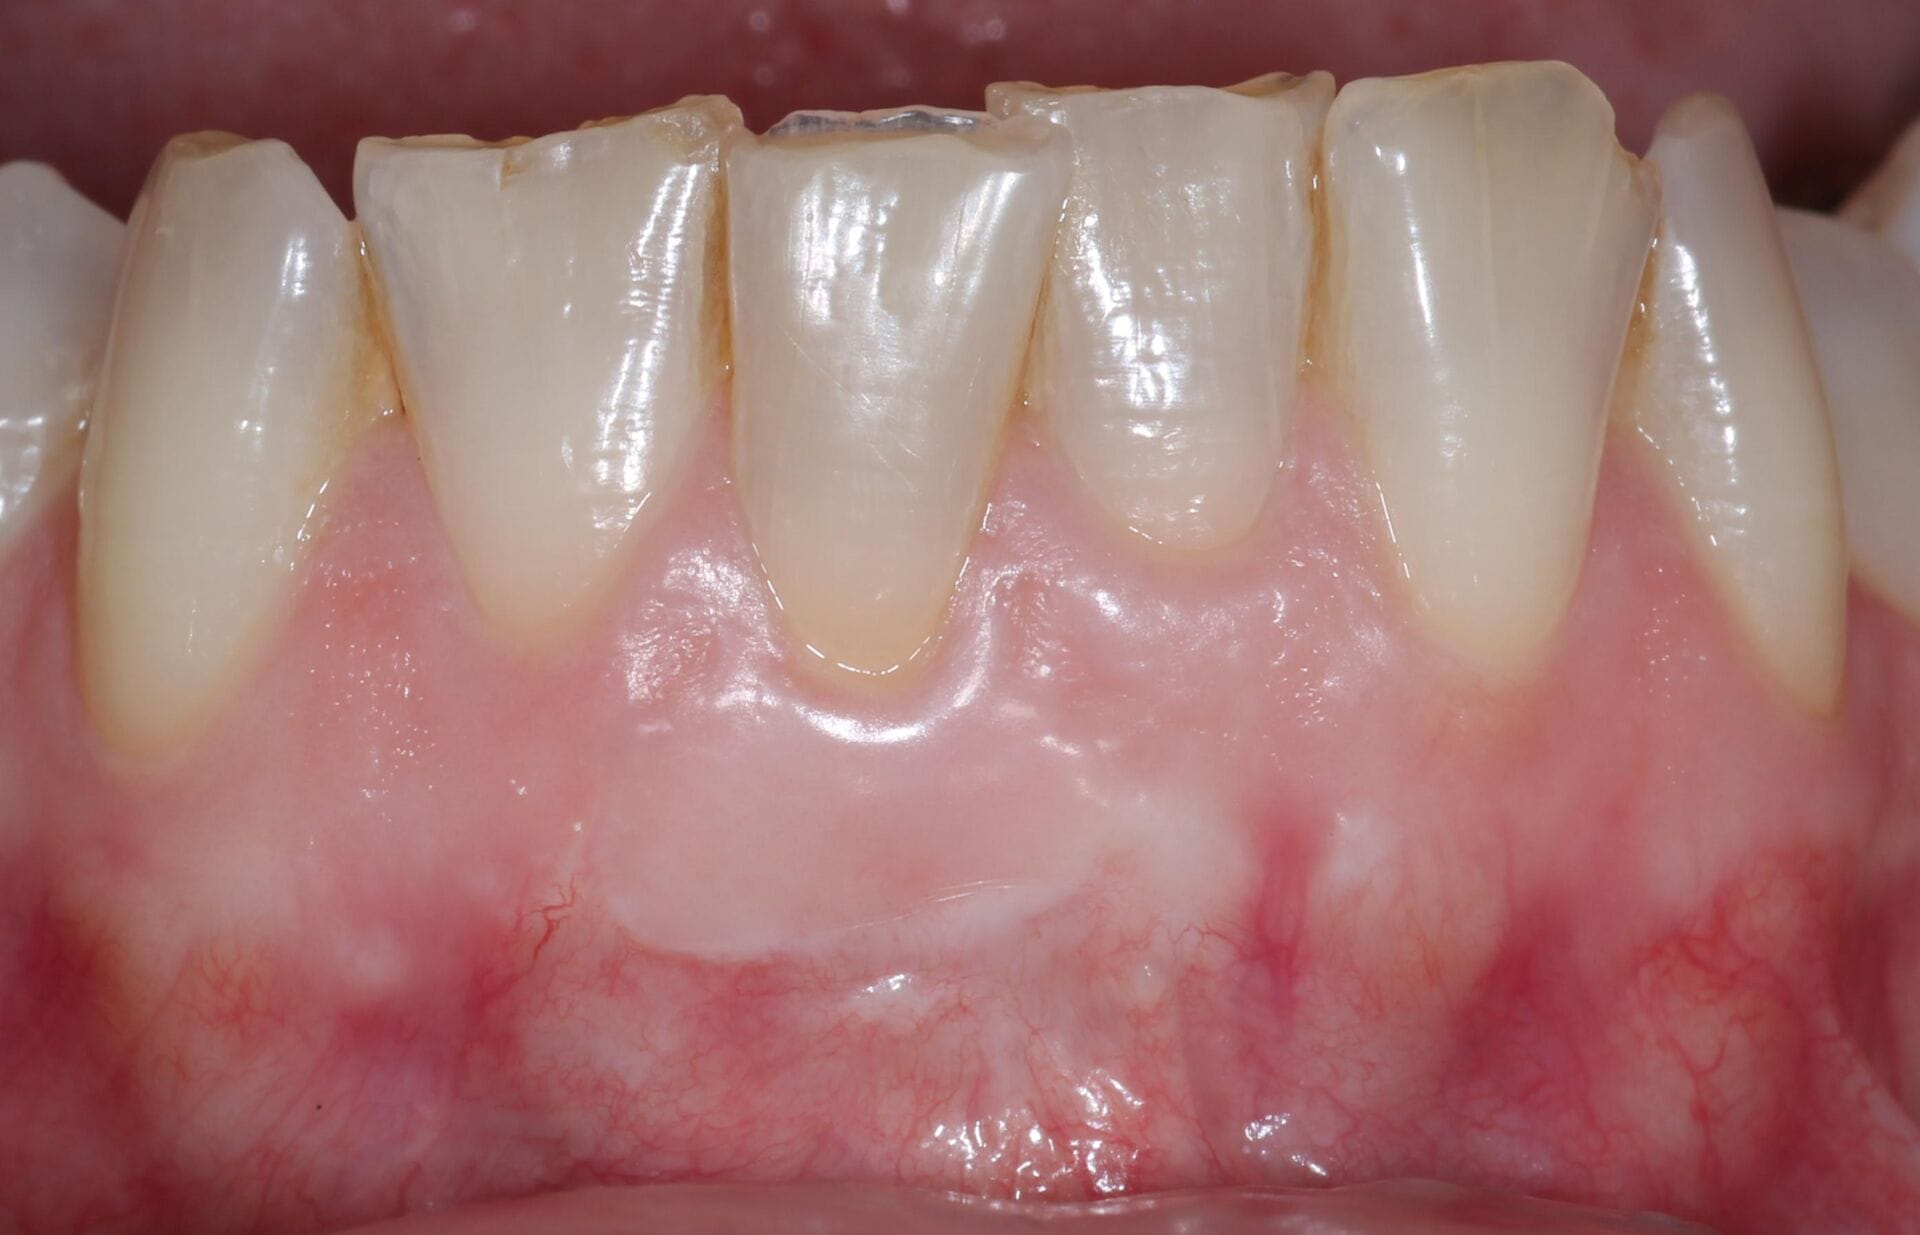

Gum recession

2.Gum Graft Surgery

In cases of gum recession, a gum graft can help restore protective tissue around the teeth. Tissue—often from the roof of your mouth—is grafted onto the affected areas, helping to reduce sensitivity, improve appearance, and prevent further recession.